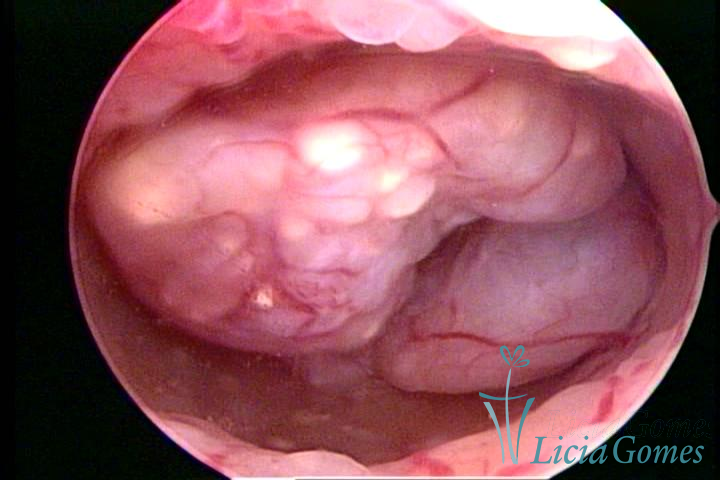

Este pode apresentar uma gama variável de aspectos macroscópicos, com aspecto pseudopolipoide; lembrando tecido cerebroide ou com reação deciduoide;a vascularização superficial é mais evidente e com vasos em formatos de saca-rolha ou espirais visualizando também a vascularização com atípias, com aumento do calibre dos vasos superficiais, pode ser encontrado também tecido em necrose, poderá haver um pequenos dendritos (papilomatoso).